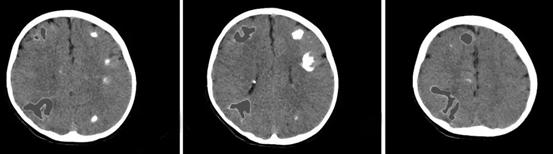

8月31日,关宇光团队为闳闳进行了手术,右侧脑部4个大的结节点被成功切除,术后患儿情况稳定,恢复良好,最让家长担心的癫痫发作也得到了有效改善,即使发热高烧到39°C,也不会出现癫痫抽搐发作,多年的心结终于放下。

术后CT示意图,右侧脑部4个大结节点(灰色阴影部分)被成功切除